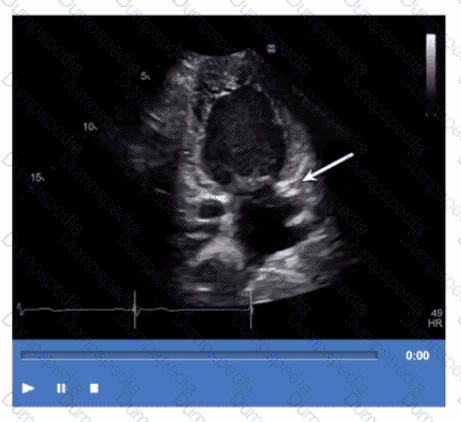

Which congenital abnormality is most consistent with the findings in this video?